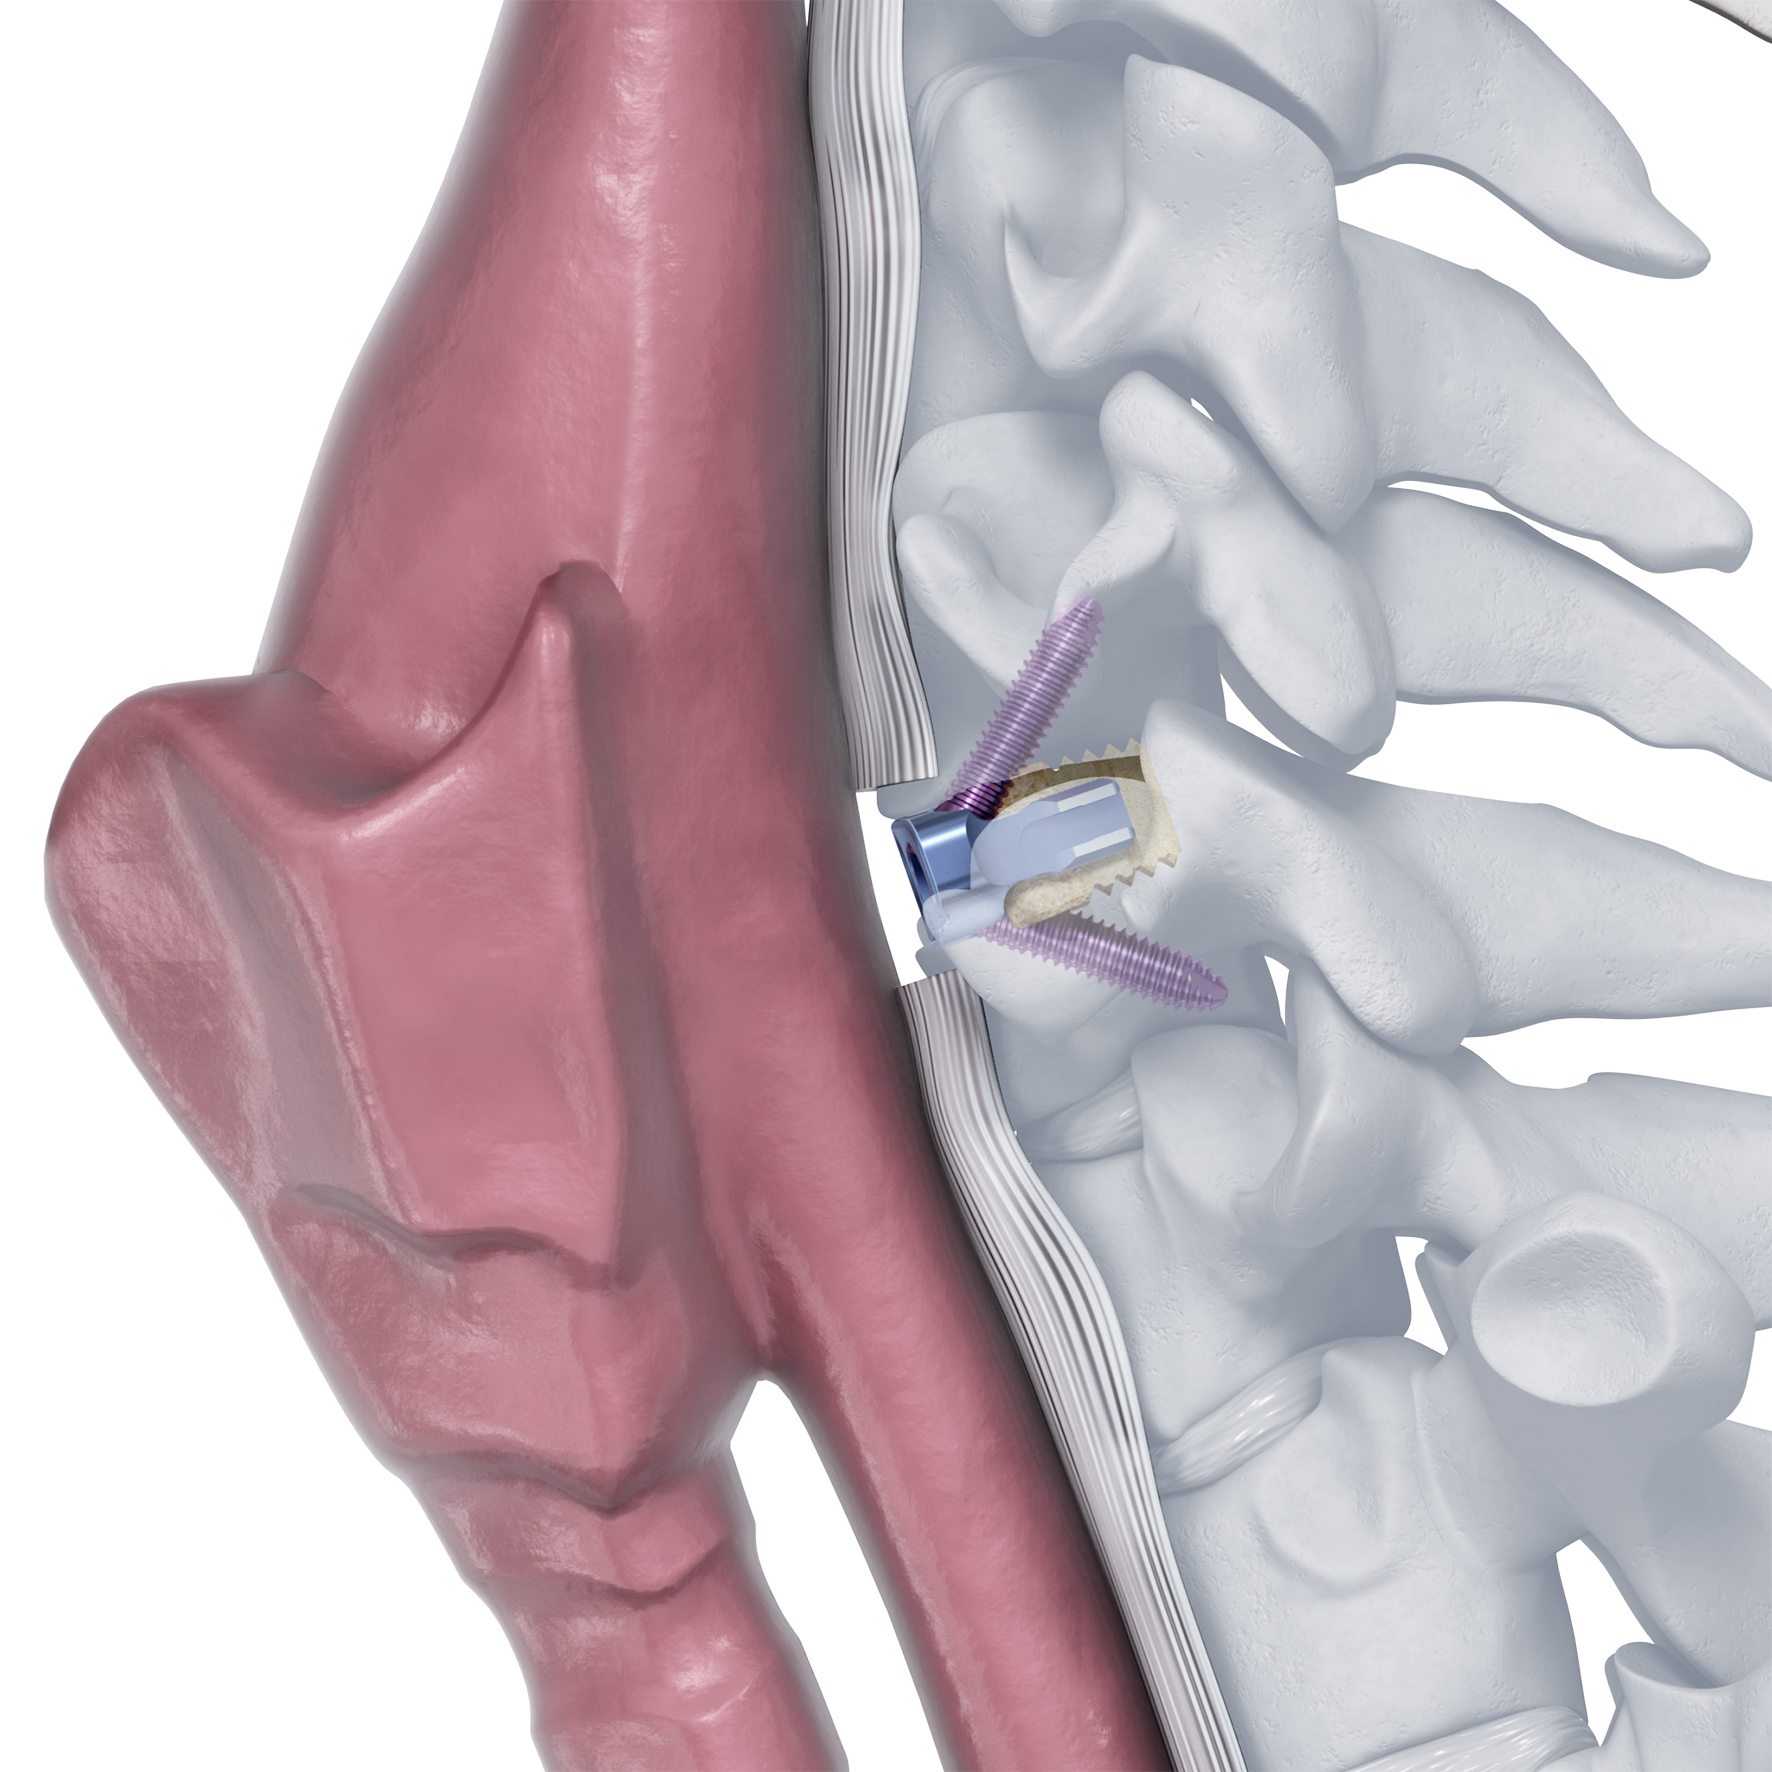

Supporting the full implant treatment process, Streamlining Additive Manufacturing For Spinal Implants,

Streamlining Additive Manufacturing For Spinal Implants, NexGen® Complete Knee Solution,

NexGen® Complete Knee Solution, Zero-P Natural Anterior Cervical Plate,

Zero-P Natural Anterior Cervical Plate, faa2dd7a270349c9ff75a7c121a888,

Improving off original VITA 46 standards, Amphenol's R-VPX, Evolution Spine New Product Launch – Ortho Spine News,